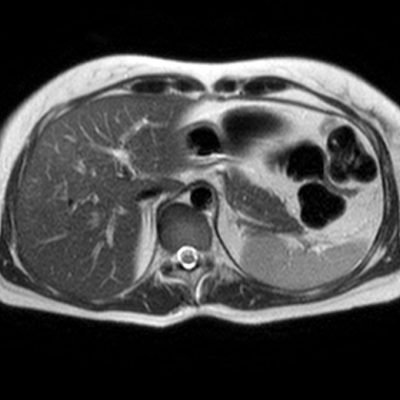

El estudio se complemento con resonancia magnética, donde se demostró la presencia de múltiples imágenes focales hepáticas confluentes con disminución de la señal en secuencias fuera de fase, no mostrando alteración de la señal en secuencias potenciadas en T2, sin signos de restricción al pulso difusión ni refuerzos anómalos luego de la administración de contraste endovenoso, estos hallazgos confirman la sospecha de esteatosis focal multinodular (fig. 5, 6 y 7).

En estos casos se recomienda realizar RM para confirmar la presencia de grasa en las “lesiones” identificadas y descartar otras etiologías, demostrando disminución de la señal en secuencias fuera de fase, sin alteración del pulso difusión (fig. 12 y 13).